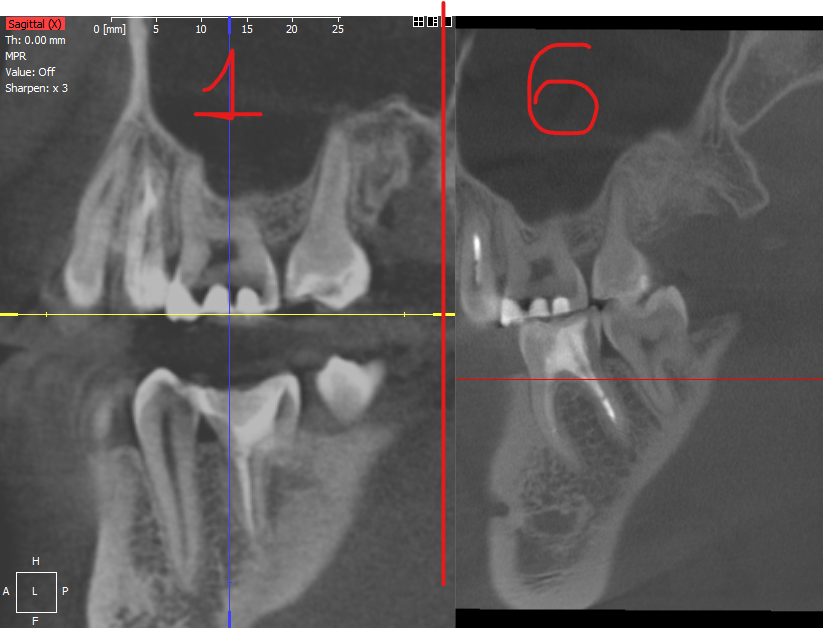

manapovdk Опубликовано 5 марта, 2023 Поделиться Опубликовано 5 марта, 2023 Пролечил поверхностный кариес, до и после лечения не делали снимок. Терапевт при расчете упоминал анестезию, коффердам, изолирующую прокладку, пломбировочный материал. Спустя месяц после лечения, я решил удалить восьмой зуб, удалил и сделал снимок. Хирург мне сказал что его тревожит мой пролеченный зуб, который я лечил месяца назад. Я его перелечивать не стал, а спустя 6 месяцев решил удалить оставшиеся три восьмерки, также сделал снимок после удаления. Снимки сравнивал, вроде спустя 6 месяцев темный участок уменьшился, но возможно это лишь разница в ракурсе и в прикусе (первый снимок сделан с тампоном, второй без и с закрытой челюстью, сделаны в разных клиниках и открыты в разных программах) Подскажите пожалуйста, врач который ставил пломбу не прочистил до конца кариес, либо данное потемнее вызвано изолирующей прокладкой? Нужно ли снова скрывать данный зуб? Ссылки на рентгеновские снимки вместе с программой: 1 месяц.rarи 6 месяц.zip Фото сравнение после 1-го месяца и 6-го месяца: Ссылка на комментарий

Женька Опубликовано 5 марта, 2023 Поделиться Опубликовано 5 марта, 2023 Здравствуйте. Вы про какой тёмный участок? Который как "квадрат" внутри серого цвета тканей? или про участки между ярко белыми? Если второе, то это скорее всего "фон", засвет томографа. Тк пломбировочные материалы имеют приличную плотность и рентгеноконтрастность. Если же первый вариант, то это пульповая камера, место где обитает нервы и сосуды зуба. Ссылка на комментарий

manapovdk Опубликовано 6 марта, 2023 Автор Поделиться Опубликовано 6 марта, 2023 @Женька Здравствуйте, спасибо вам за ответ! Я про участки между ярко белыми, если пломбировочные материалы рентгеноконтрастны, то и потемнения не должно быть? Ссылка на комментарий

red_butler Опубликовано 6 марта, 2023 Поделиться Опубликовано 6 марта, 2023 это артефакт Ссылка на комментарий